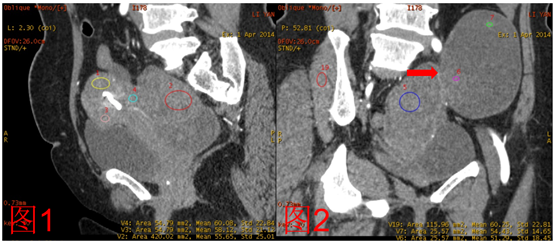

CT表现: 盆腔巨大实性、囊实性占位 实性病变与子宫分界不清,轻度强化 囊实性病变以囊性结构为主,其内见少量不规则实性成分,强化程度较实性病变稍弱,整个病变似与实性病变有分隔(图2 红色箭头) 常规CT诊断: 结合病史,实性病变考虑子宫肌瘤复发 囊实性病变性质待定,子宫肌瘤复发?卵巢病变?

能谱曲线分析: 动脉期实性病灶及囊实性病灶中实性成分的能谱曲线与子宫肌层能谱曲线基本一致,考虑病变来源于子宫肌层; 延迟期子宫肌层能谱曲线与实性病灶及囊实性病灶中实性成分的能谱曲线出现分离,位置稍高,但实性病灶及囊实性病灶中实性成分的能谱曲线基本一致,考虑两者性质一致

能谱单能量分析: 低keV血管成像显示,实性病灶及囊实性病灶中实性成分的供血动脉均为子宫动脉

最后诊断: 盆腔实性、囊实性病变考虑子宫肌瘤复发 小结: 能谱曲线可以进行同源性分析,即通过能谱曲线的相似与否来提示病变是否有相似性。但需要注意的是使用能谱曲线时要用动态的思维来考量。例如:该病例的动脉期与延迟期的能谱曲线的变化既说明病灶的起源相似性,又说明病灶供血的特征性,为临床提供了更多的病变信息,指导临床诊疗方案的制定。 单能量低kev,可以使原来难以结构清晰显示,为临床提供更多的病变信息。 病例来源:中国贵航集团302医院